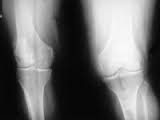

Correlation between clinical and radiological grading of osteoarthritis